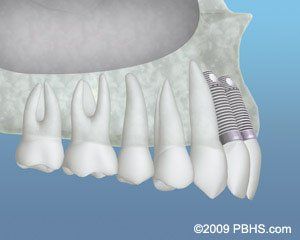

Jaw Bone Loss

The jawbone is associated with or reabsorbed with missing teeth atrophies over a period of time. This often leaves a condition in which there is poor quality and quantity of bone suitable for placing dental implants.

In these circumstances, most patients are not candidates for dental implant placement. Today we have the capacity to grow bone where it is required.

About Bone Grafting

Due to prior extractions, gum disease or wounds, bone grafting can repair implant sites with the insufficient bone structure.

Your treating doctor uses synthetic bone, which gives great results. Sometime your own bone may be used and taken from the jaw. Sinus bone grafts (sinus lifts) are usually performed to replace bone in the upper jaw.

In addition, special membranes may be utilized under the gum to protect the bone graft and encourage bone regeneration. These membranes may or may not dissolve, depending on Dr. Amanda Piche or Dr. Dominik Dubravec's professional opinion to achieve the best outcome.

This is called guided bone regeneration or guided tissue regeneration.